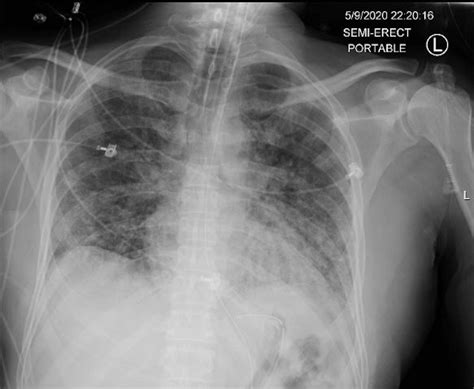

ARDS is a complex syndrome that can be triggered by various factors, including sepsis, pneumonia, trauma, and aspiration. It is marked by the rapid onset of bilateral pulmonary infiltrates, refractory hypoxemia, and decreased lung compliance. The Ards Chest X Ray is instrumental in visualizing these pulmonary infiltrates, which appear as diffuse, bilateral opacities on the radiograph.

The Ards Chest X Ray is often the first imaging modality used to evaluate patients suspected of having ARDS. It provides a quick and relatively inexpensive way to assess the lungs for signs of inflammation and edema. Key findings on an Ards Chest X Ray include:

• Bilateral pulmonary infiltrates

• Diffuse opacities

• Air bronchograms (air-filled bronchi surrounded by consolidated lung tissue)

• Absence of pleural effusions or cardiomegaly

These findings, when combined with clinical criteria such as the PaO2/FiO2 ratio (the ratio of arterial oxygen partial pressure to fractional inspired oxygen), help confirm the diagnosis of ARDS.

• Bilateral Infiltrates: ARDS typically presents with bilateral, diffuse infiltrates that are often more pronounced in the dependent lung zones.

• Air Bronchograms: These are visible air-filled bronchi within consolidated lung tissue and are a hallmark of ARDS.

• Absence of Pleural Effusions: Unlike other causes of pulmonary edema, ARDS is usually not associated with significant pleural effusions.

• Cardiomegaly: The heart size is typically normal in ARDS, helping to differentiate it from cardiogenic pulmonary edema.